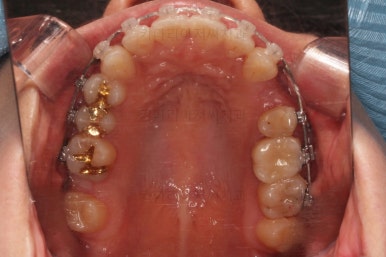

윗니도 발치를 했고요.

발치공간을 서서히 줄여 나갑니다.

입매 변화도 신중하게 체크합니다.

윗니는 어느 정도 틈이 많이 줄었는데요. 아랫니는 기약이 없죠.

이때가 교정을 시작한지 8개월이 지난 시점인데요.

이제 미니스크류가 등장합니다.

상하좌우 발치 공간의 크기와 위치가 제각각이라서 당겨지는 양과 속도가 차이납니다.

그래서 미니스크류를 반드시 써줘야 합니다.